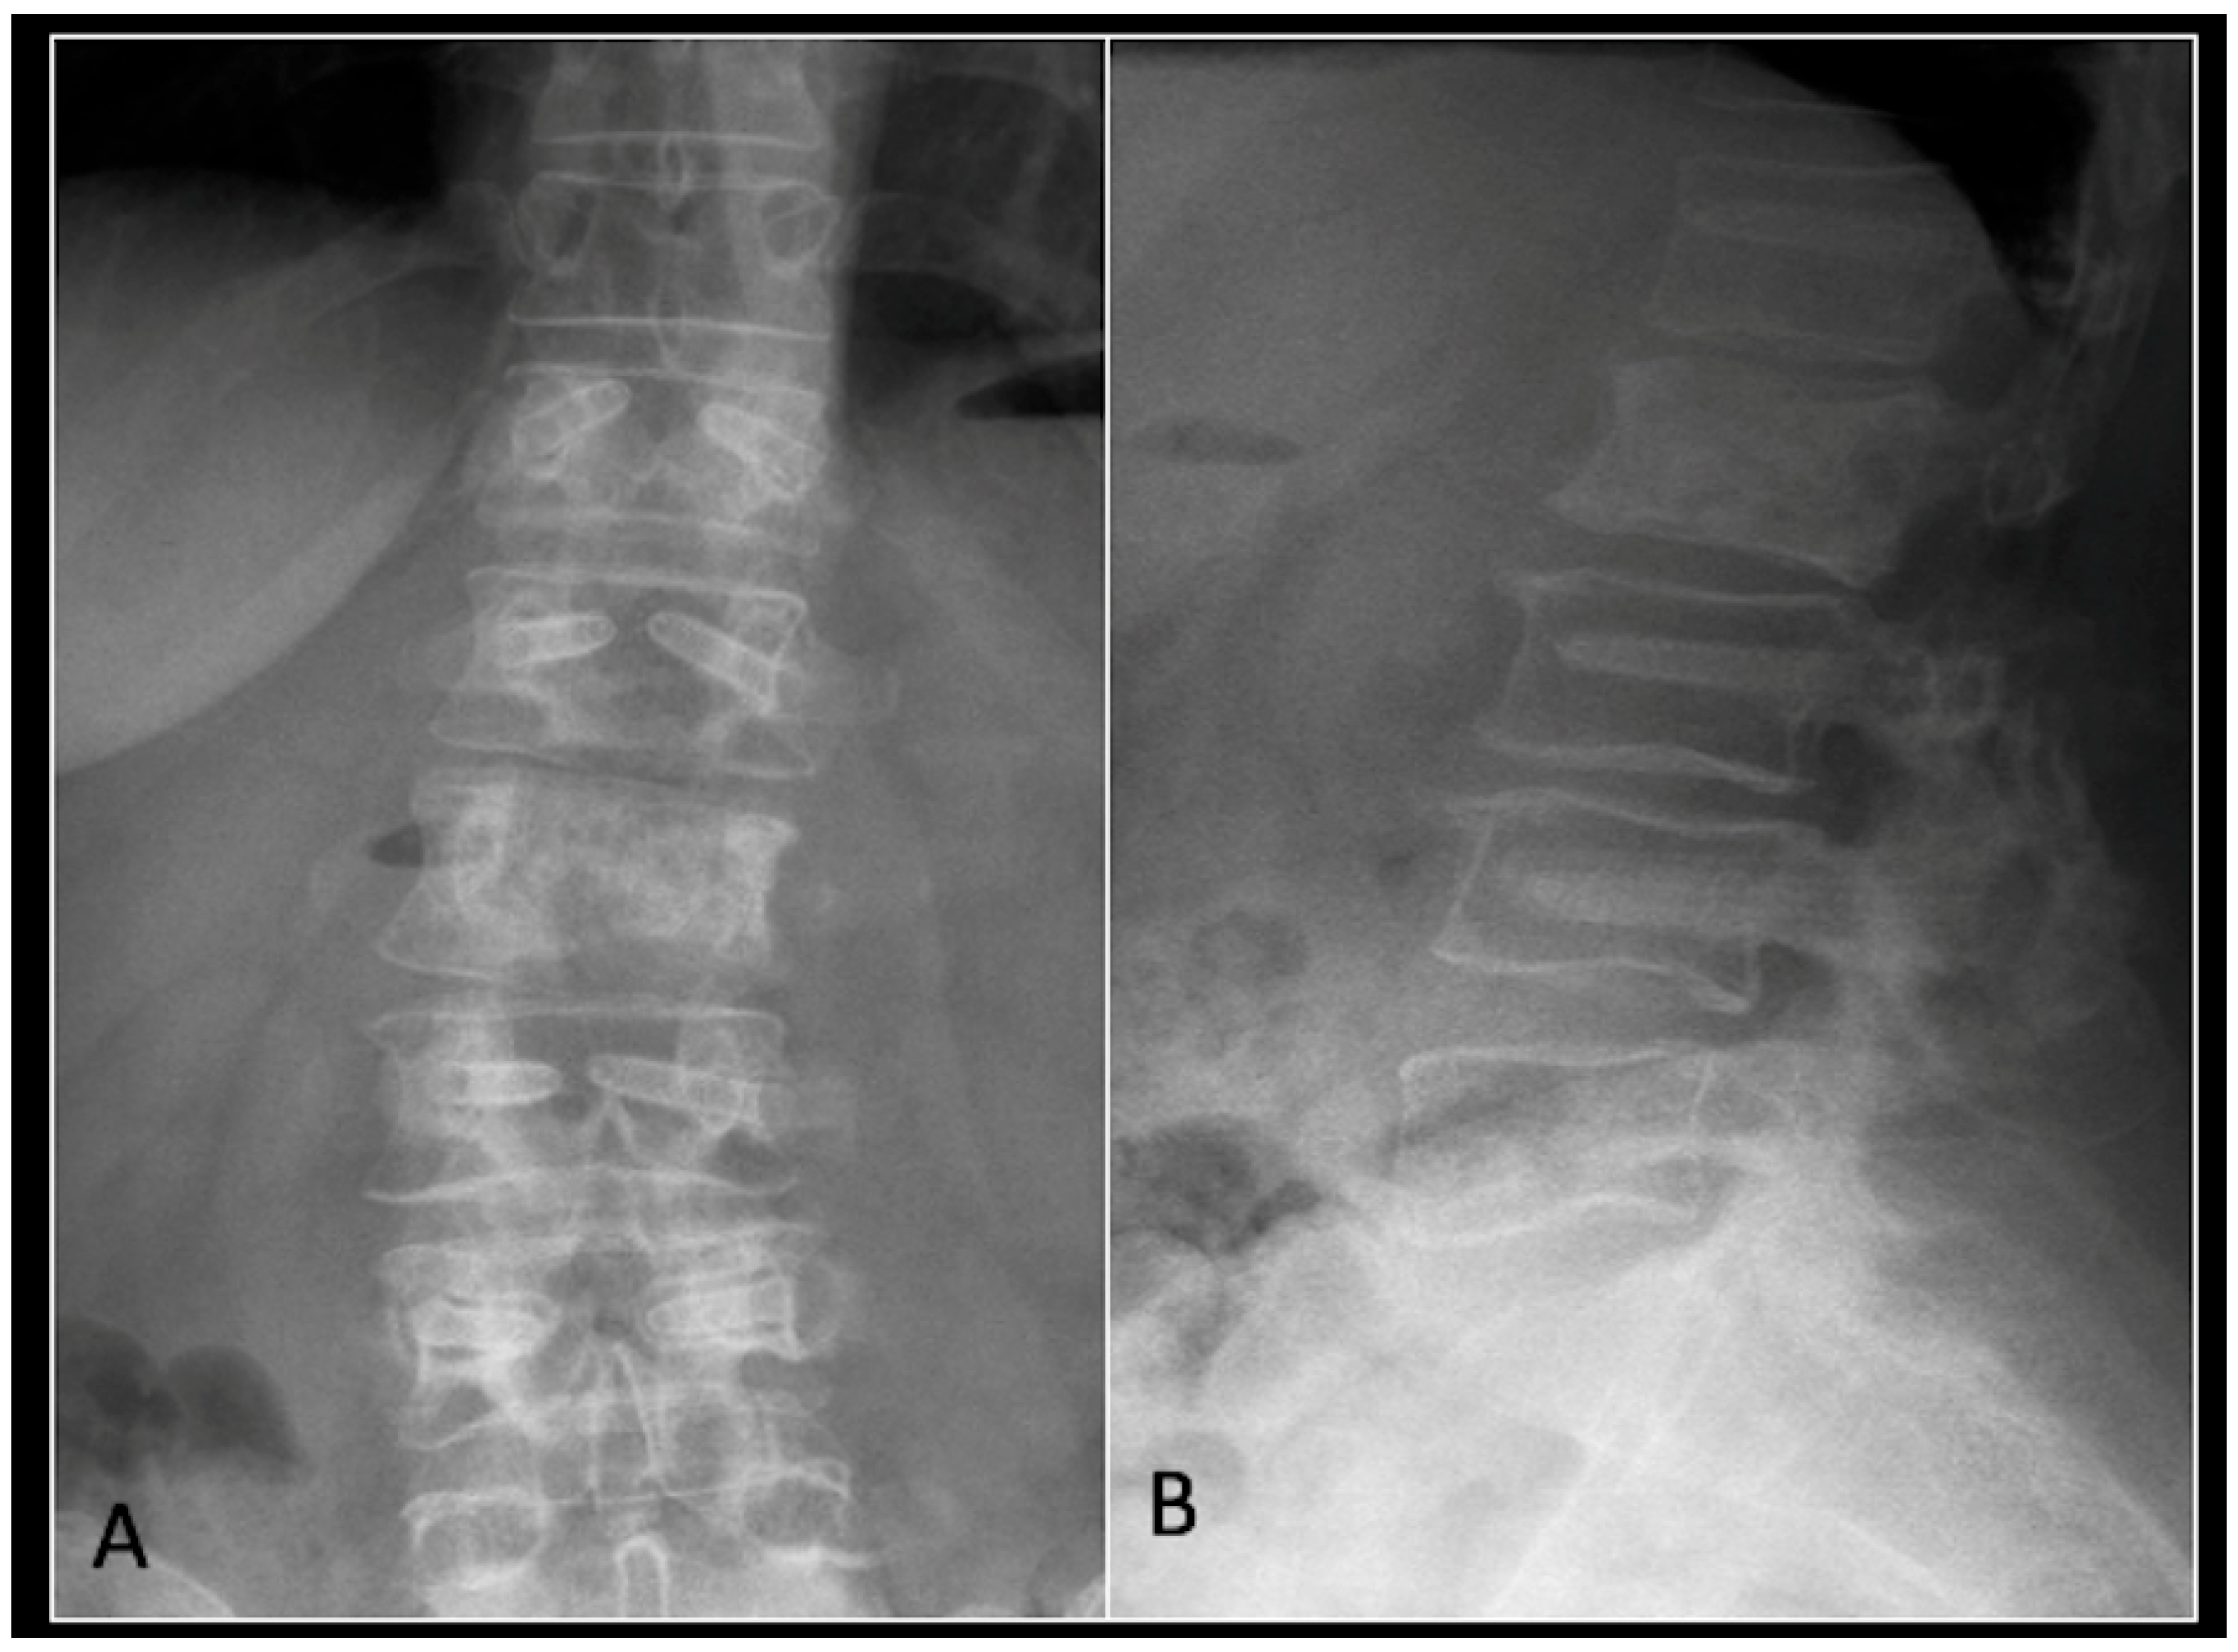

This 56-year-old lady was diagnosed with a biopsy-confirmed L2 chordoma (Figure 11). She underwent posterior decompressive separation surgery and instrumental stabilisation T12-L4 using carbon-based implants (Figure 12). Surveillance imaging at 6 months and 12 months post-separation did not show any progression of residual tumour disease (Figure 13 and Figure 14).

Figure 12.

(A) demonstrates an anteroposterior view, and (B) illustrates a lateral standing radiograph of the lumbosacral spine demonstrating carbon-based posterior instrumentation.